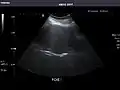

Aorta

Aorta: Visualized portions normal in caliber, 16 x 15 mm.